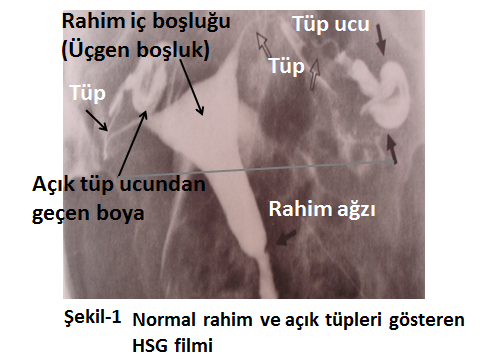

Aşağıda farklı HSG görüntüleri ile konu görsel hale getirilmeye çalışılmıştır.

Şekil-1’de normal bir HSG filminin görüntüsü izlenmektedir. Görüleceği üzere rahim iç boşluğu üçgen şeklinde olup, normaldir. Her iki tüpten de boyalı madde geçişi olup tüpler açıktır.